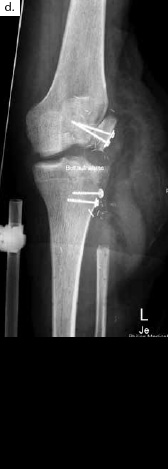

Ein 28-jähriger Motorradfahrer kollidierte mit einem Pkw und erlitt eine Defektfraktur der linken proximalen Fibula und einen Verlust der lateralen Femurkondyle inklusive des lateralen Bandapparates unter einem extrem großen Weichteildefekt (Abb. 2a u. b). Nach multiplen auswärtigen Debridements wurde nach Zuweisung ins eigene Haus interdisziplinär besprochen, die Extremität mit einer Kniegelenkprothese und einer plastisch-chirurgischen Defektdeckung zu erhalten. In einem ersten Schritt wurde ein kontralateraler Tensor-fasciae-latae-(TFL-) Lappen umschnitten („flap delay“), um ihn in seiner gesamten Länge vom Beckenkamm bis zum Knie heben zu können. Eine Woche später erfolgte die Konstruktion der fabrizierten Chimärlappenplastik durch Hebung des osteofasziokutanen TFL-Transplantats inklusive eines vaskularisierten Beckenkammblocks und der mikrovaskuläre Anschluss End-zu-End an den Serratusabgang der A. thoracodorsalis des rechten muskulokutanen M.-latissimus-dorsi-Lappens (Abb. 2c). Dieses sehr große zweiblättrige Lappenmodul wurde anschließend End-zu-End an die Vasa gastrocnemia lateralis anastomosiert und die vaskularisierten Einzelkomponenten wie folgt verteilt: Der Beckenkammblock fungierte als laterale Kondylenaugmentation, um den Sitz einer späteren Knieendoprothese zu optimieren; die Faszia lata wurde zur Stabilisierung von diesem Block transossär an die verbleibende Fibula und das laterale Tibiamassiv genäht (Abb. 2d). Die ausgedehnten Lappenplastiken dienten zum Defektverschluss, gemeinsam mit zusätzlichen Spalthauttransplantaten (Abb. 2e). Nach sechswöchiger Abheilung im Fixateur externe erfolgten der Umschulungsbeginn und die Mobilisation an Unterarmgehstützen mit Fußsohlenteilkontakt.